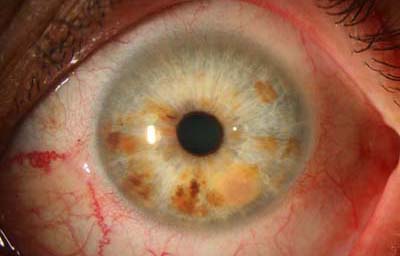

En la forma difusa, se aprecia una capa plana, irregular, de células pigmentadas o no, con un compromiso del iris confluente o multifocal; representa el 10% de todos los melanomas del iris. Su diagnóstico es difícil y demorado, porque frecuentemente los pacientes están siendo tratados por el cuadro de glaucoma secundario que generan. Clínicamente lo mas frecuente en su presentación es encontrar heterocromía hipercrómica unilateral y glaucoma secundario. Como dato importante, los melanomas difusos comparandolos a otros melanomas del iris, muy frecuentemente están compuestos por células epiteliodes, que tienen poca cohesión y se dispersan con facilidad en el humor acuoso, haciendo siembras en el trabéculo y estroma iridiano, y por esta razón son considerados de alto riesgo para metástasis. (33)

Melanoma difuso del iris

Archivo Fotográfico Dr. Francisco Barraquer.

Melanoma difuso del iris

Archivo Fotográfico Dr. Francisco Barraquer.